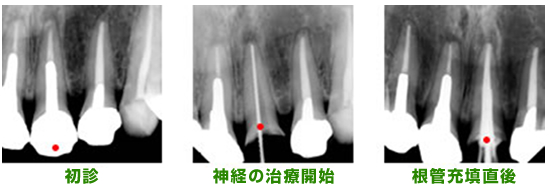

レントゲンを見てみると歯根の先までお薬が詰めてないため、本来お薬が詰まるはずのところに空間ができてしまい、細菌の繁殖が繰り返されてしまいます。

その結果、歯根の先には膿の袋ができて、炎症が骨の中で広がってしまいます。(写真上)

元々詰めてあったお薬を除去し(写真左)、歯根の中を消毒します(写真中央)。お薬は歯根の先まで加圧しながら、詰めていきます(写真右)。

正確にお薬を詰め終わると、歯根の中で細菌の繁殖場所がなくなり、膿(うみ)の袋は徐々に消失します。